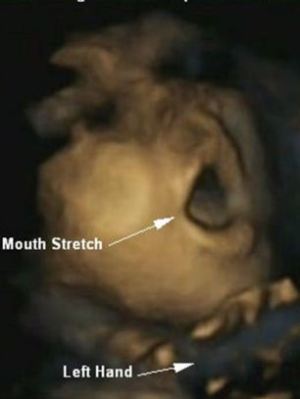

Ψυχολόγοι εντόπισαν ότι τα έμβρυα έχουν τη δυνατότητα, όσο αναπτύσσονται και στα τελευταία στάδια της εγκυμοσύνης, να προβλέπουν και όχι απλά να αντιδρούν στις κινήσεις των χεριών τους προς το στόμα τους. Παράδειγμα τέτοιας πρόβλεψης αποτελεί το άνοιγμα του στόματος πριν την είσοδο του δαχτύλου.

Τα ευρήματα αυτά προέκυψαν από τη μελέτη «υπερηχογραφημάτων 4D», δηλαδή τρισδιάστατων υπερηχογραφημάτων που μπορούν να ιδωθούν σε πραγματικό χρόνο, για την απεικόνιση 8 κοριτσιών και 7 αγοριών μεταξύ της 24ης και 36ης εβδομάδας κύησης.